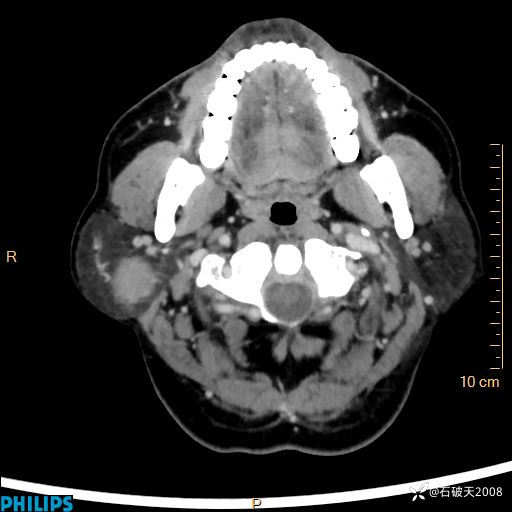

病例分享:颈部占位,一周后公布病理

男 57岁 主 诉:发现右侧颌下肿物1月余。

现病史:1月余前家属发现右侧颌下肿物。局部皮肤无红肿、热痛,无吞咽困难,无异物感,无恶心、呕吐,无头痛、头晕,无胸闷、胸痛,无发热、咳嗽、咳痰及呼吸困难。于我院行体表肿块彩超检查(2024.03.15我院)示:右侧耳下皮下软组织内低回声,未治疗。今为进一步治疗门诊以“腮腺肿瘤”为诊断收住我科,发病来患者神志清,精神可,饮食、睡眠及大小便正常,体重无明显下降。

平扫